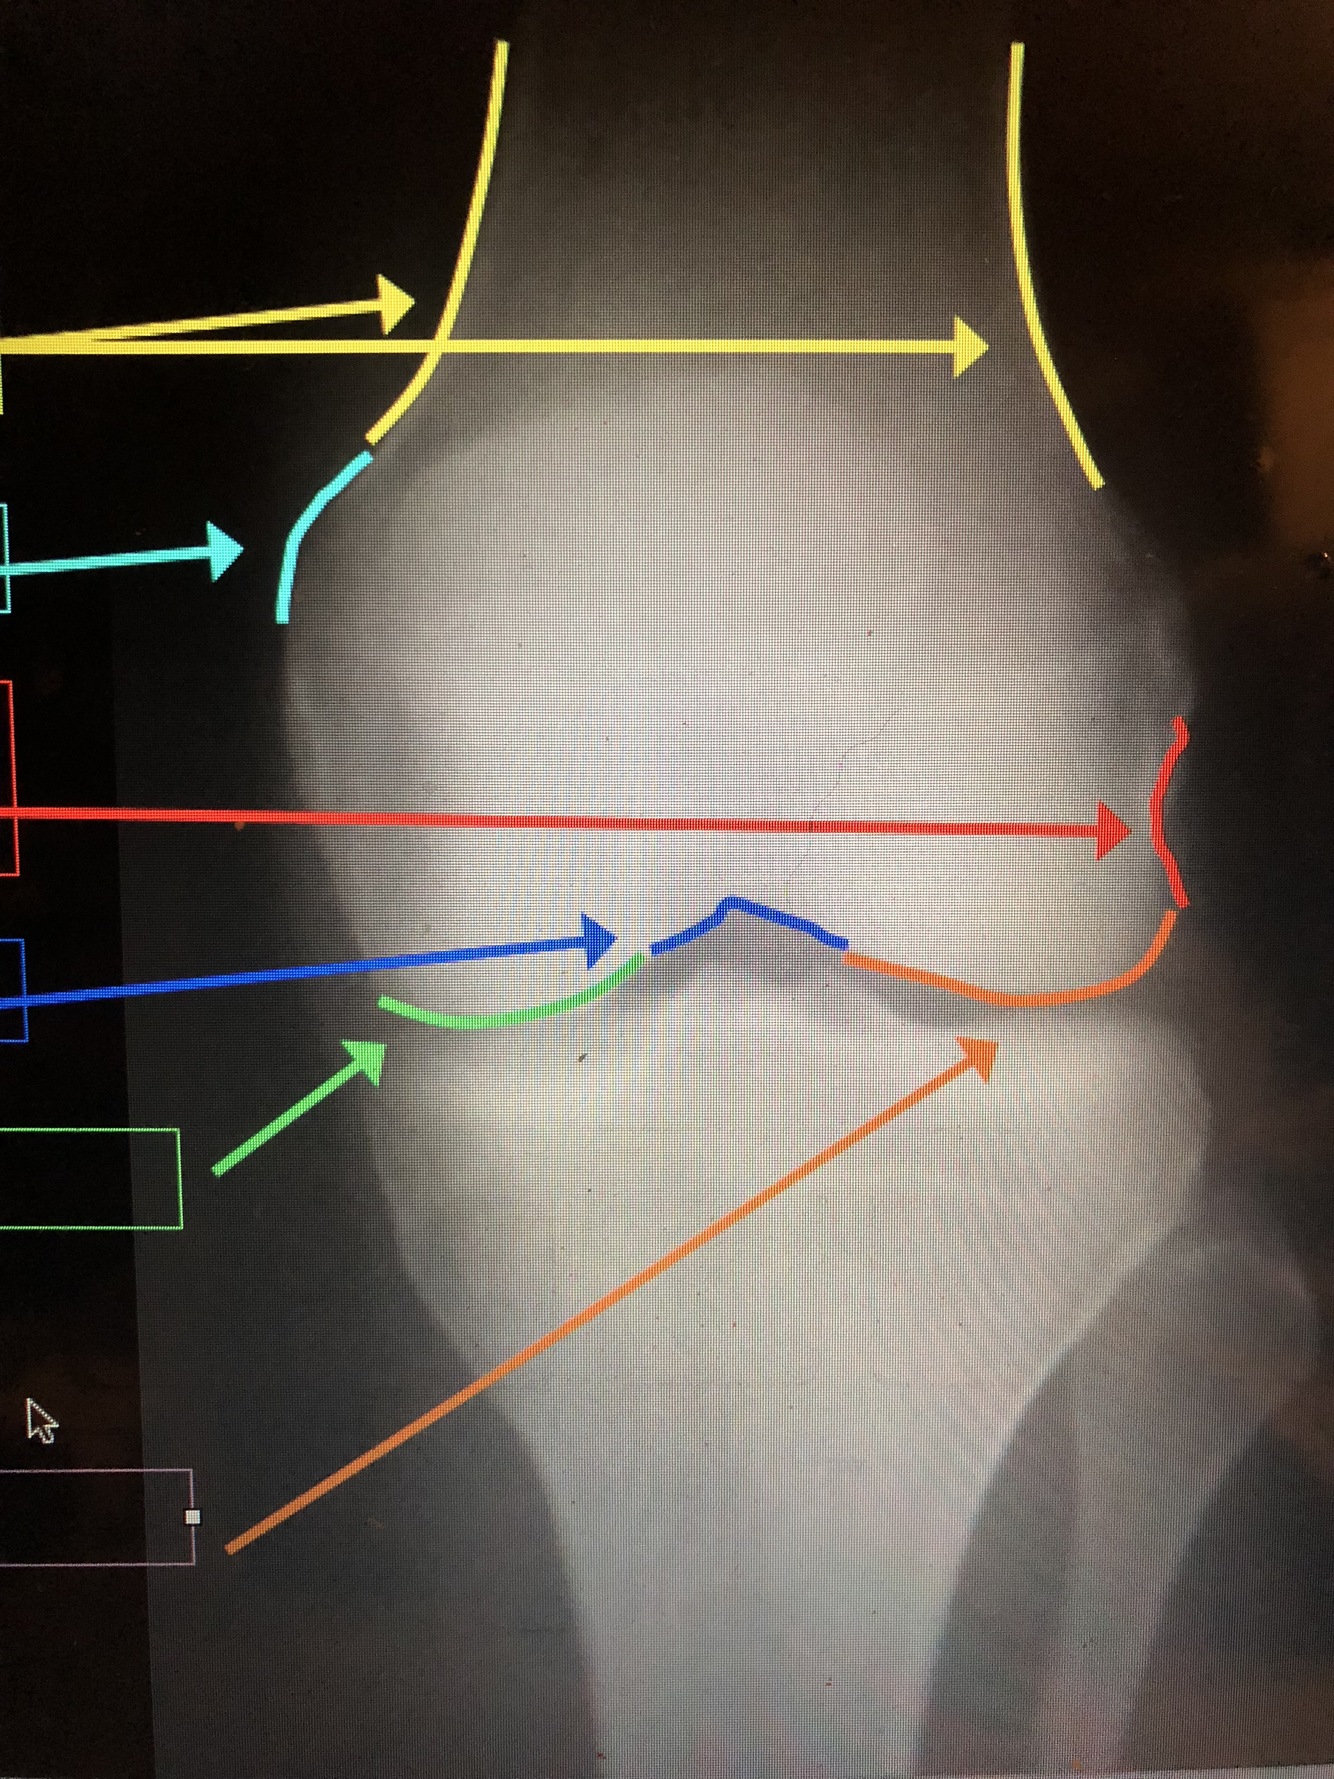

what is the yellow line?

Cortex – thickest at the diaphysis, but thins out near the metaphysis at the epicondyles

What is the dark blue lines?

Epicondyles (med. & lat.)

What are the yellow lines?

Supracondylar Ridge/Line (med. & lat.)

What is the red line?

Popliteal Groove – where popliteal tendon passes

What is the dark blue line?

Intercondylar Notch

What is the green line?

Medial Femoral Condyle

What is the orange line?

Lateral Femoral Condyle